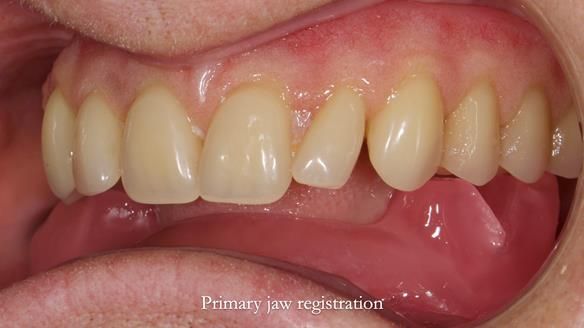

However, once Rowan and I reviewed the remaining metal crown on tooth 46, we realised it would make an ideal abutment for a gasket denture. By reshaping the lingual surface of the crown, we created an excellent gasket seal.

This approach worked far better than the proposed ring-clasp design - improving retention, comfort, and aesthetics while keeping the design clean and simple.